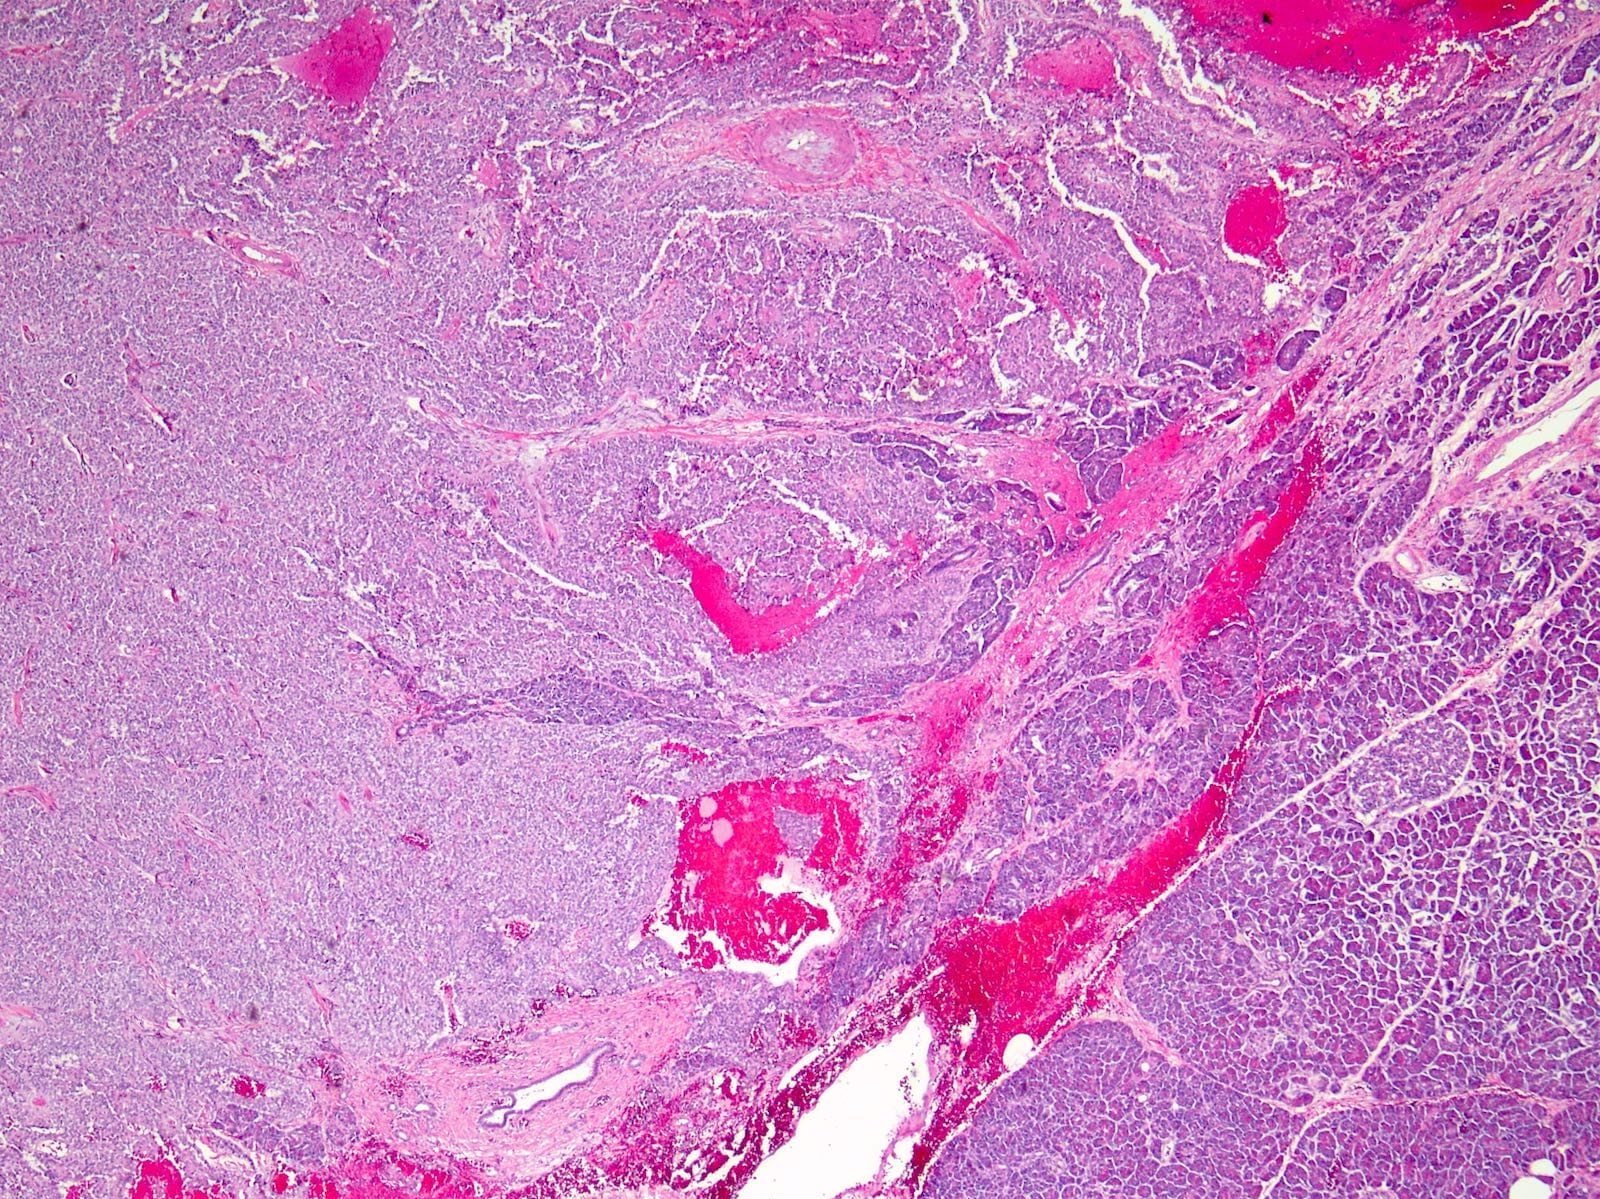

Microscopic (histologic) description

- Tumors are heterogeneous, with variable admixture of solid and pseudopapillary areas

- Solid areas are comprised of uniform cells admixed with capillary sized blood vessels

- Pseudopapillae are formed due to tumor cells getting detached from blood vessels forming fibrovascular stalks or rosette-like structures (Arch Pathol Lab Med 2020;144:829)

- Stroma usually shows various degrees of hyalinization or evidence of degeneration, such as hemorrhage, foamy macrophages, calcification and cholesterol clefts

- Tumor cells usually have a moderate amount of eosinophilic cytoplasm with intracytoplasmic hyaline globules (PAS+ and diastase resistant, positive for alpha-1-antitrypsin) and perinuclear vacuoles (Am J Surg Pathol 2011;35:981)

- Relatively uniform nuclei with finely textured chromatin, inconspicuous nucleoli and characteristic longitudinal grooves

- Variants include clear cell, oncocytic and pleomorphic

- Rare mitotic figures

- Although grossly well circumscribed, microscopic finding of infiltration to the surrounding pancreatic tissue is not uncommon

- Rare cases of highly aggressive behavior; histological features in those cases included diffuse growth pattern, extensive necrosis, significant nuclear atypia, high mitotic count (35 - 70/50 high power fields) or sarcomatoid features (Am J Surg Pathol 2005;29:512)

Microscopic (histologic) images

Contributed by Monika Vyas, M.D., Omid Savari, M.D. and Raul S. Gonzalez, M.D.